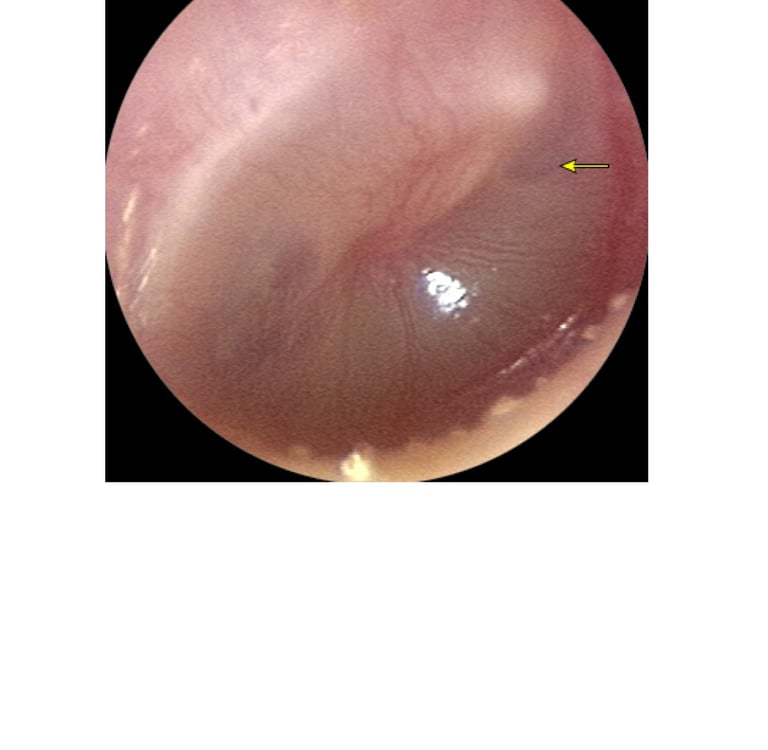

• segni obiettivi di infiammazione della membrana timpanica (iperemia marcata, estroflessione),

• presenza di essudato endotimpanico (MT sporgente o otorrea da perforazione spontanea).

La sola iperemia della MT, la perdita del triangolo luminoso o la retrazione timpanica

non sono sufficienti per la diagnosi e indicano più probabilmente un’otite media effusiva (OME).

A. Otite media acuta precoce con infiammazione.

B. Versamento purulento con livello di aria e liquido.

C. Versamento purulento sporgente che riempie l'orecchio medio.